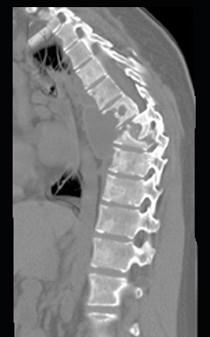

问题 男,34岁,发热,背部疼痛,不能直立,局部软组织肿胀,结合图像,最可能的诊断是 ( )

选项 A、骨肉瘤 B、成骨肉瘤 C、脊柱结核 D、脊柱转移瘤 E、化脓性骨髓炎

答案 E